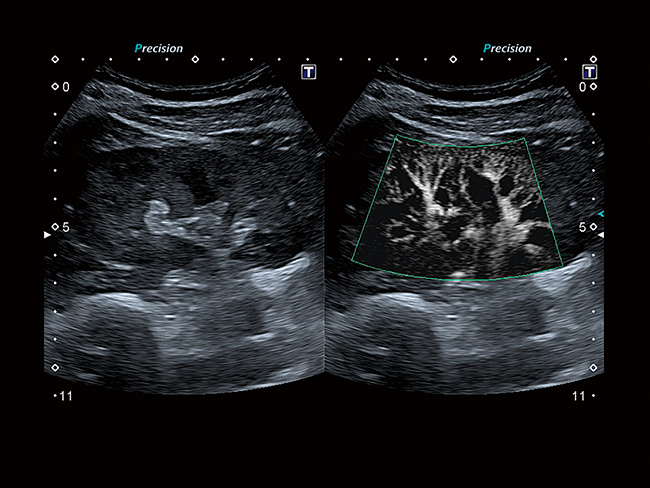

Усовершенствованный динамический поток (ADF) поднимает цветную допплеровскую визуализацию на совершенно новый уровень пространственного разрешения. Позволяет исследовать мелкую сосудистую сеть с беспрецедентной точностью и детализацией.

Видя невидимое

Превосходная микрососудистая визуализация (SMI) расширяет диапазон видимого кровотока для визуализации микрососудистого кровотока с высокой частотой кадров, повышая диагностическую достоверность при оценке поражений, кист и опухолей.